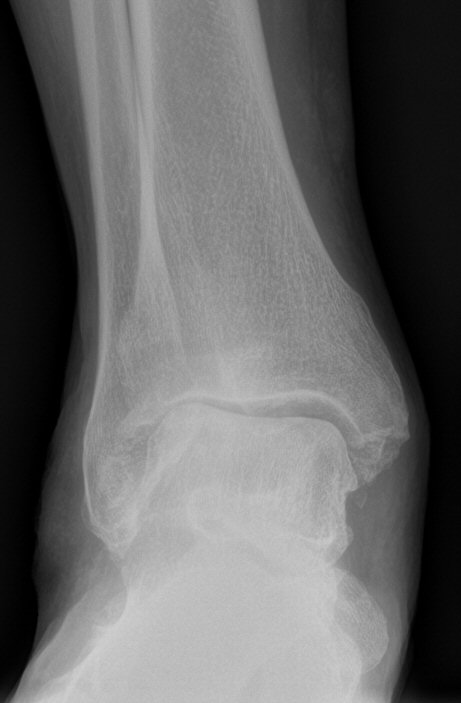

Klassificering

Takakura: [2]

- Stadie I: Osteofyter men bevarad ledspringa

- Stadie II: Minskad ledspringa men ej benkontakt

- Stadie IIIA: Benkontakt vid mediala malleolen

- Stadie IIIB: Benkontakt talus-troklea mot tibia

- Stadie IV: Komplett benkontakt

- Belastad slätröntgen, inför beslut om protes eller tibiaosteotomi så belastad slätröntgen med "long axial view".

Lateral artros, kan vara aktuell för vinkelkorrigerande tibiaosteotomi